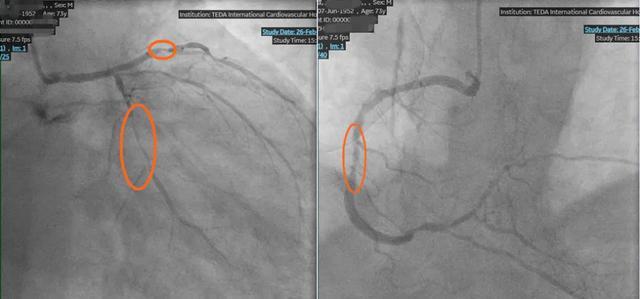

更棘手的是,周先生不仅有30年高血压、3年糖尿病史,长期的基础病让他的血管条件变得极差。冠脉造影结果更让人揪心:心脏的三根主要血管(前降支、回旋支、右冠状动脉)全部严重狭窄,最关键的生命线%,随时可能因急性缺血引发心肌梗死甚至心脏骤停。这种三支病变叠加心功能极差的情况,属于典型的复杂、高危病变。患者合并症多,传统外科搭桥手术风险极高,常规介入手术也极易因血流波动引发心脏骤停等恶性事件,治疗一度陷入两难。

王永德主任团队利用宝贵的窗口期,凭借精湛技术,分别对堵塞严重的左前降支、左回旋支、右冠状动脉的多处严重狭窄病变部位进行球囊扩张和支架植入。

术后造影显示,原本几乎堵死的血管被成功打通,血流恢复通畅。周先生胸闷、憋气、夜间憋醒的症状彻底消失,精神状态也明显好转。